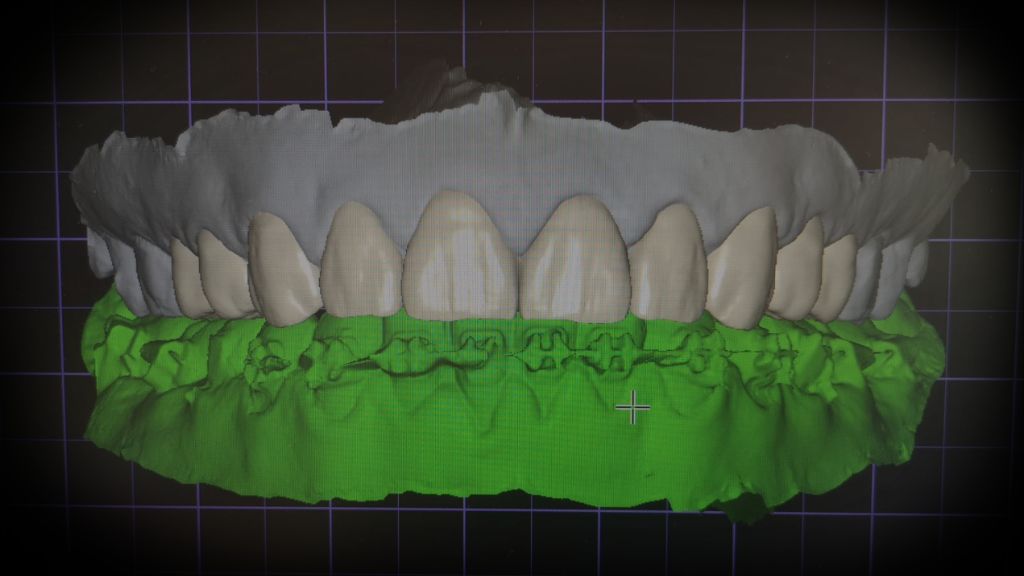

La Dra. Gil utiliza tecnología de última generación, como el diseño de sonrisa, para ofrecer resultados precisos y personalizados, asegurando que cada sonrisa sea única y refleje la esencia del paciente. Su enfoque integral combina ciencia y arte para lograr sonrisas naturales que no solo mejoran la estética, sino también la autoestima y el bienestar general.

Por otro lado, el uso de tecnología avanzada como el diseño de sonrisa 3D permite a los pacientes visualizar el resultado final antes de comenzar el tratamiento, brindando mayor confianza y seguridad durante todo el proceso.

En la clínica de la Dra. Carolina Gil, el uso de tecnología avanzada es fundamental para garantizar resultados precisos y personalizados en el diseño de sonrisa. Las innovaciones tecnológicas permiten un enfoque más detallado y controlado, asegurando que cada paciente obtenga una sonrisa que se adapte perfectamente a sus rasgos faciales y necesidades estéticas. Dos de las principales herramientas que se emplean en este proceso son el escáner digital de sonrisa y el diseño de sonrisa 3D.

Escáner Digital de Sonrisa: Máxima Precisión

El escáner digital de sonrisa es una herramienta de última generación que permite obtener imágenes detalladas y tridimensionales de la boca del paciente sin la necesidad de moldes tradicionales. Este escaneo captura de manera precisa la estructura dental, las encías y la mordida, proporcionando una visión clara y exacta de la sonrisa actual del paciente. Gracias a esta tecnología, es posible planificar con exactitud los pasos a seguir para transformar la sonrisa.

Diseño de Sonrisa 3D: Visualización del Resultado Final

El diseño de sonrisa 3D es una herramienta digital que permite a los pacientes visualizar cómo será su sonrisa antes de que comience el tratamiento. Con este software, se crea un modelo digital del resultado esperado, permitiendo ajustes y personalizaciones antes de cualquier intervención. Esto brinda a los pacientes mayor tranquilidad y confianza, ya que pueden ver cómo su sonrisa cambiará y asegurarse de que el resultado cumpla con sus expectativas.

Rehabilitación Oral con Tecnología Avanzada

La rehabilitación oral también se beneficia de estas tecnologías. En casos donde se requiere una restauración completa de la función y estética dental, el uso del escáner digital y el diseño 3D asegura que los tratamientos sean más precisos y efectivos. Esta tecnología no solo mejora el aspecto estético, sino que también contribuye a una mejor funcionalidad de los dientes, ya sea mediante la colocación de implantes dentales, carillas o coronas.

El uso de estas herramientas avanzadas en la clínica de la Dra. Carolina Gil asegura que el tratamiento de diseño de sonrisa sea lo más cómodo, eficiente y predecible posible, garantizando resultados de alta calidad y una sonrisa que transforma la vida de los pacientes.

Cada tratamiento se define durante la consulta de valoración, donde la Dra. Carolina Gil y el Dr. Carlos Castro evalúan la situación dental del paciente, discuten sus expectativas y diseñan un plan que garantice una sonrisa natural y armoniosa. La tecnología de diseño de sonrisa 3D permite visualizar el resultado antes de iniciar el tratamiento, ofreciendo una visión clara y precisa del resultado final.